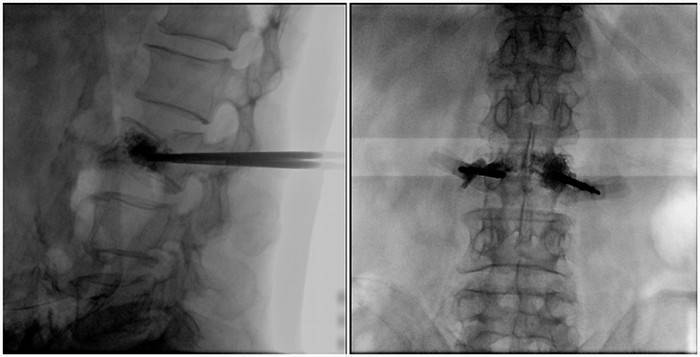

(2)术中切口5毫米,借助大视野平板C臂机PLX119C的高清图像,确定进针的方向及进针的深度。经椎弓根向椎体置管,建立通道,插入骨扩张器(球囊)。球囊扩张恢复椎体高度,并在椎体内形成空腔,确定骨水泥的注入剂量,并注入骨水泥观察其扩散情况。

大平板C臂机的高清图像

(3)注射过程需要C臂透视来查看骨水泥的分布情况,预防骨水泥外露进入椎管内引起神经损伤。椎骨体内骨水泥填充完好以后,拔出工作套筒按压止血,并继续俯卧位十分钟,等待骨水泥硬化,最终手术圆满完成。